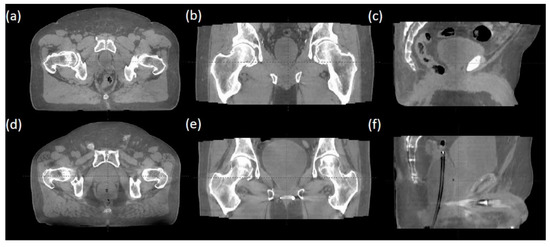

- Jarema, T.; Aland, T. Using the iterative kV CBCT reconstruction on the Varian Halcyon linear accelerator for radiation therapy planning for pelvis patients. Phys. Medica 2019, 68, 112–116. [Google Scholar] [CrossRef] [PubMed]